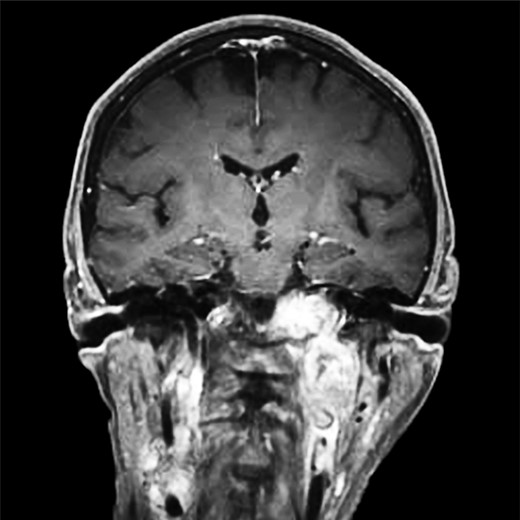

Repeat magnetic resonance imaging (Figs. 3 and 4) showed increased left-sided carotid PGL, significant extension into the jugular foramen and skull base, and associated high-grade tumor compromise of the left internal carotid artery; no radiologic evidence suggested intracranial ischemic sequelae. Computed tomographic (CT) imaging showed infiltration of the left petrous and clivus regions of the skull (Fig. 5). Findings were compatible with progression of the previously known tumor.

(A and B) Magnetic resonance images, sagittal and coronal planes, show increased left-sided carotid PGL, with significant extension into the jugular foramen and skull base.

Magnetic resonance angiogram, coronal plane, shows tumor compromise of the left internal carotid artery.